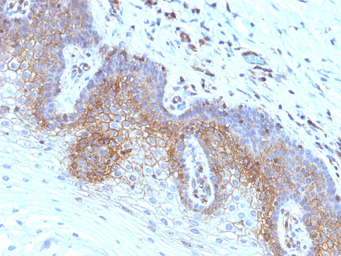

IHC-P analysis of human cervical carcinoma tissue using GTX34436 beta 2 Microglobulin antibody [SPM617].